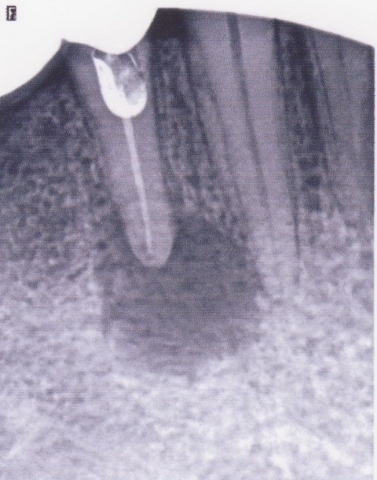

Примеры лечения радикулярных кист челюстей без скальпеля:

Фото: до лечения депофорезом

Фото: после лечения депофорезом